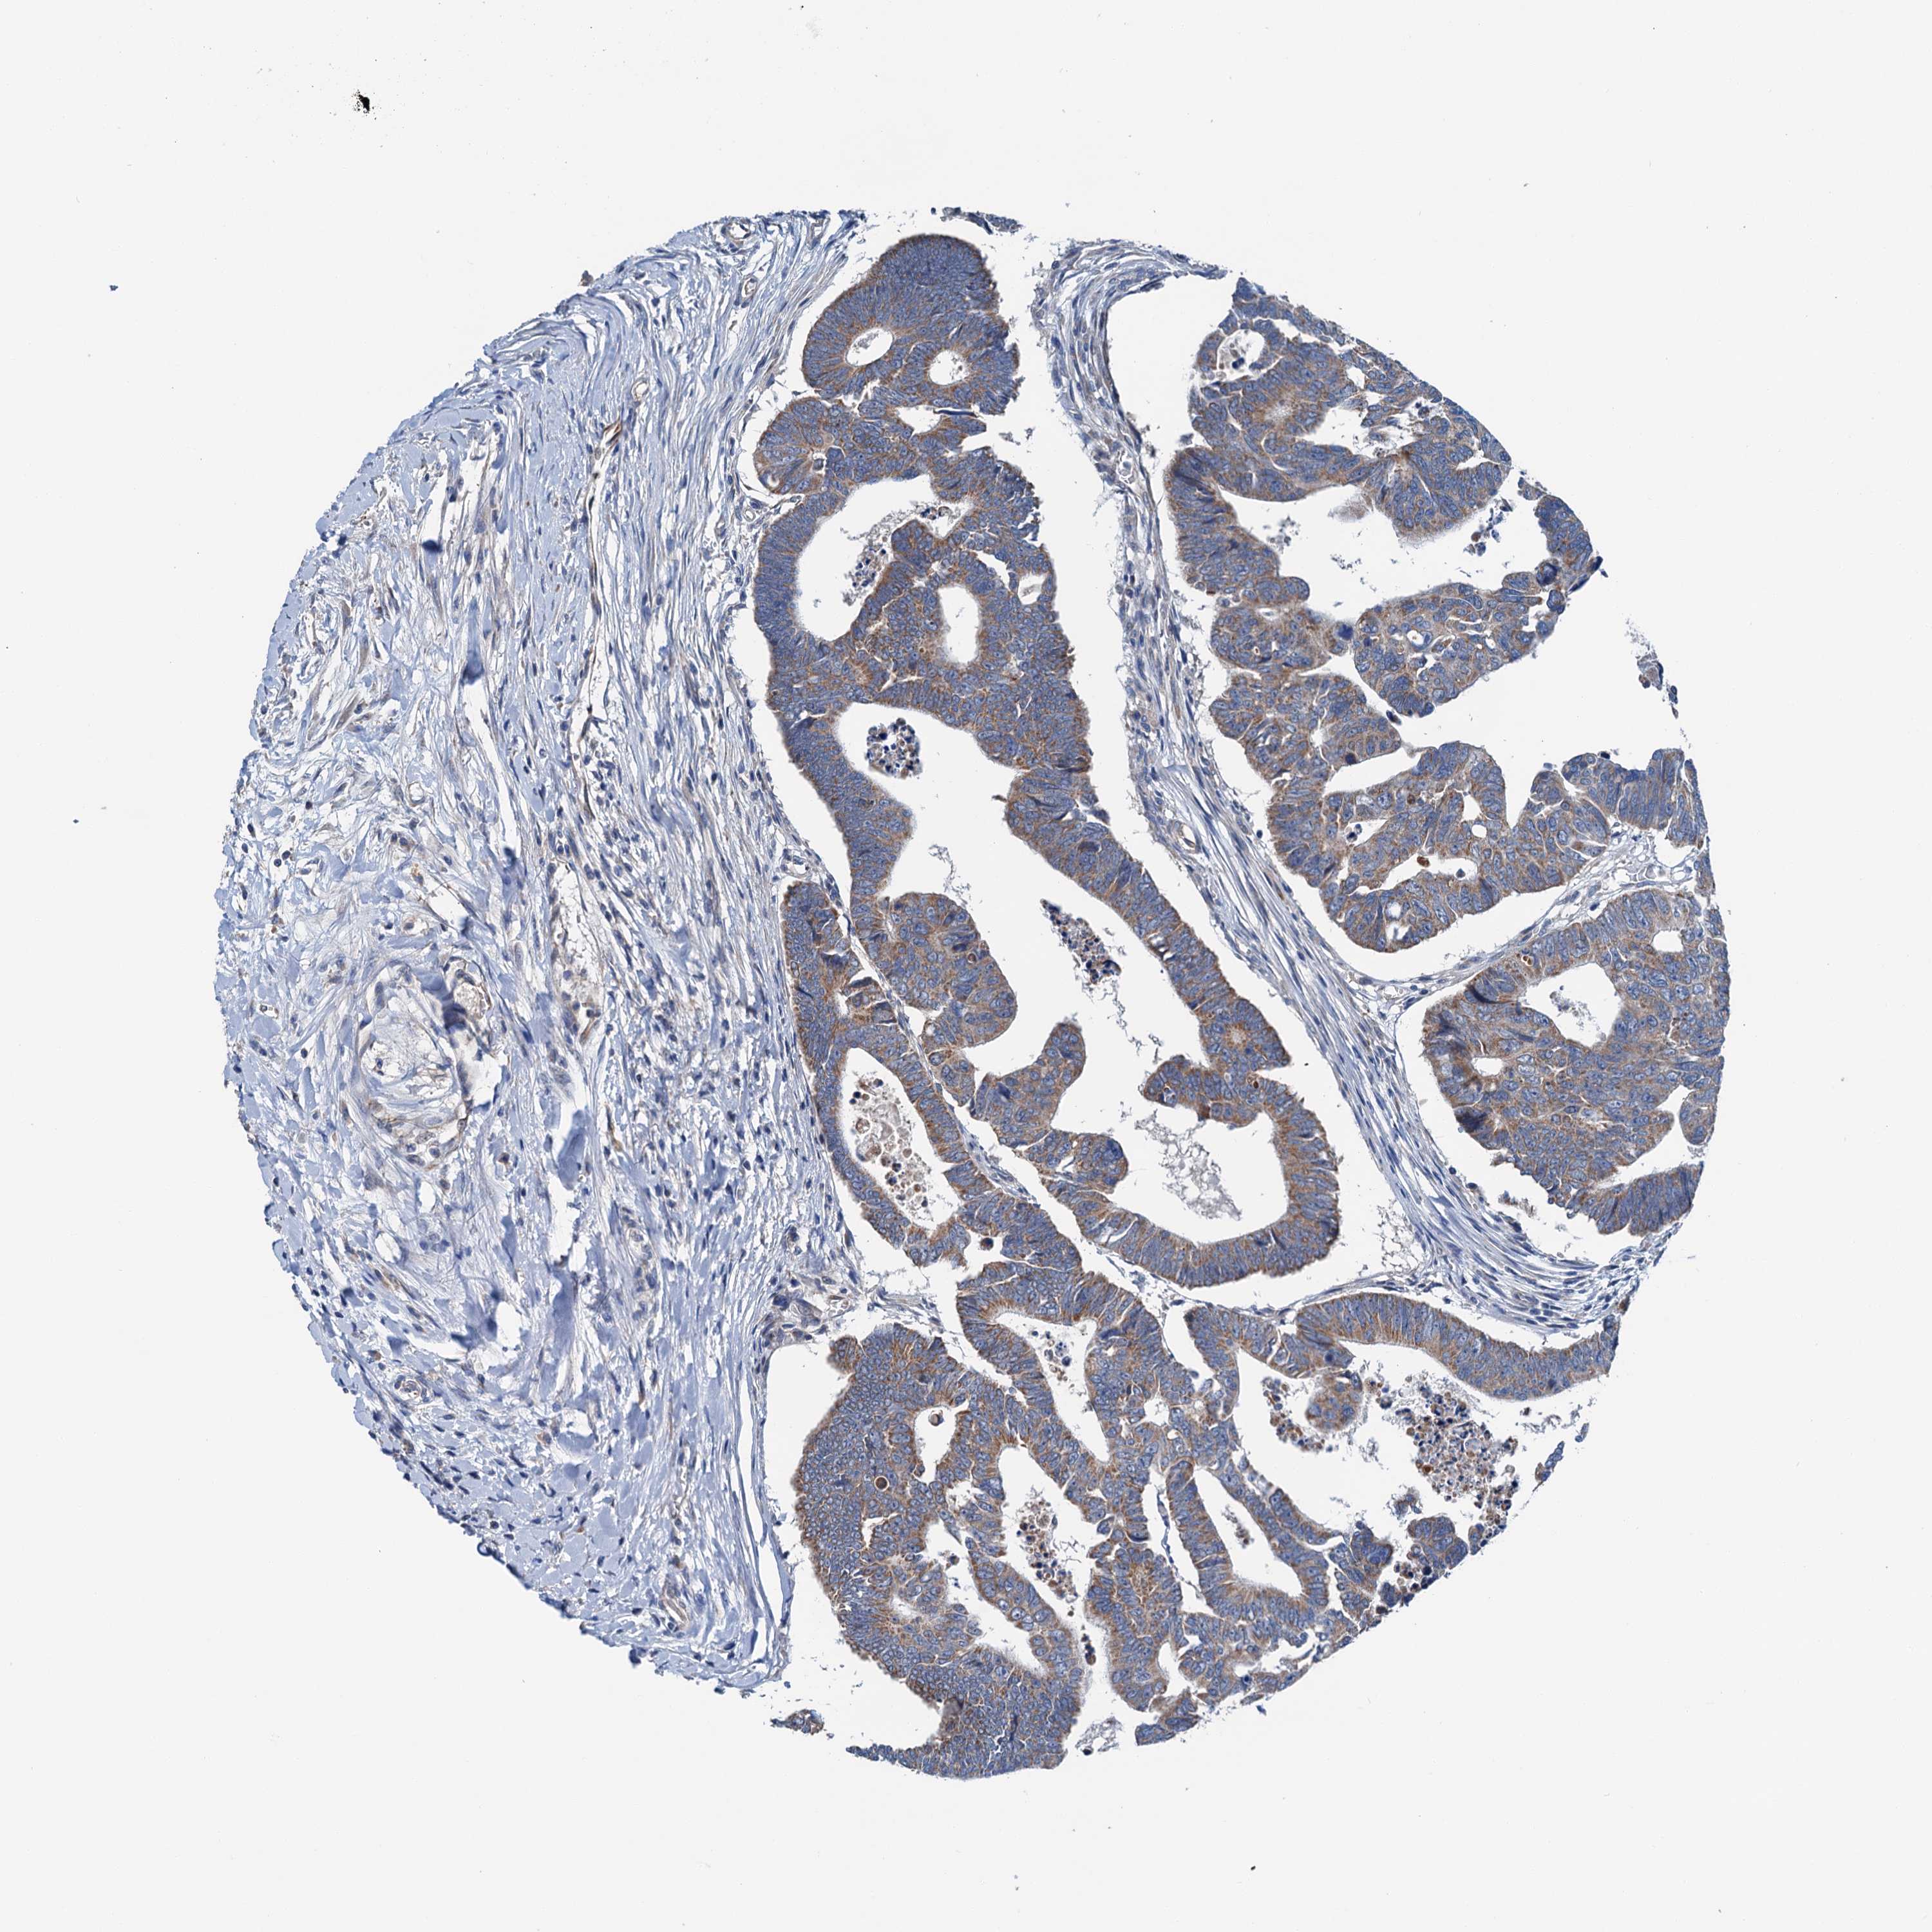

CANCER COLORECTAL CANCER Show tissue menu

Colorectal cancer

Human cancer

Colon adenocarcinoma